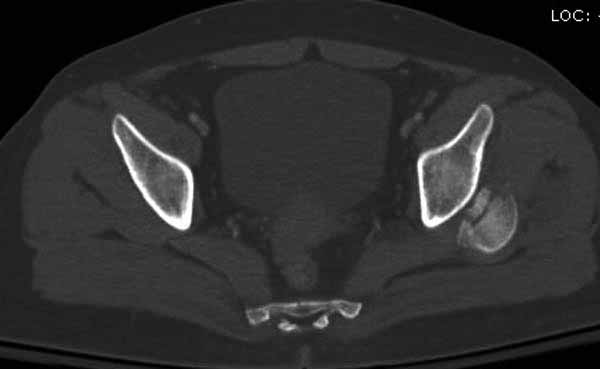

В диагноз еще необходимо внести закрытую (?) ротационно-нестабильную травму таза с переломами лонных седалищных костей, боковой массы крестца справа.

Вообщем.., больная поступает около 2.00 дня и дальнейщая хронология: 2.27 PМ рентген грудной клетки; 2.54 РМ рентген бедра; 2.53-3.06 КТ скан, всего около 2000 срезов. Из-за беспокойства пациента (алкоголь), множественные переломы ребер – трубка в превральную полость и интубация. Около 3.45 в операционной эксплуараторная лапароскопия с последующим ушиванием брюшной полости.

Перелом позвоночника и боковую компрессию таза отнесли к стабильным переломам и не стали форсировать события до лучших времен...